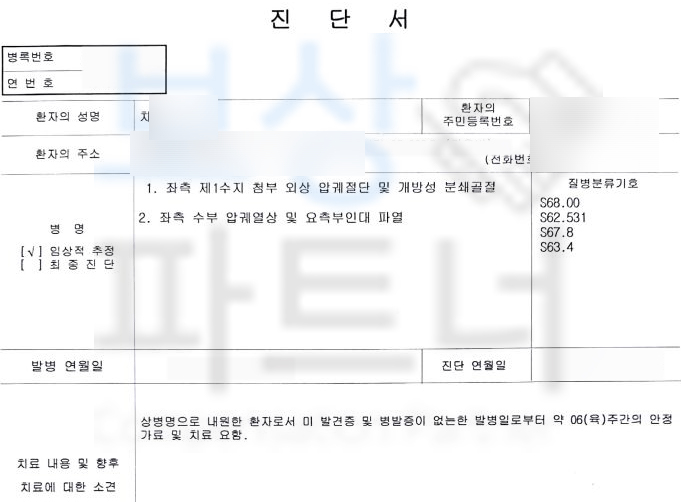

엄지손가락이 분쇄 골절의 형태로 골절되는 사고를 당하셨습니다. 아래의 사진은 사고 당시 엑스선 사진입니다.

위 사고로 차@@님은 엄지손가락에 핀고정을 하는 금속 고정술을 받게 되셨고 다행히도 엄지손가락의 형태가 유지되어 잘 수술을 받으셨습니다.

산재 장해등급 13급!!** 일시금 99일**의 총 장해급여 5,544,297원입니다. 보험사에 후유장해보험금 청구를 위해서는 의료 전문의의 후유 장해 진단서가 필요합니다.

저희는 공신력 있는 대학병원의 전문의를 통해 후유 장해 평가를 진행하였고 이를 기초로 작성한 손해사정서와 각종 서류를 각 보험사에 송부하였습니다.

물론 보험사의 내부 자문을 거치며 약 1달간의 시간이 소요되었지만 결국 저희가 처음 청구한 제1수지 뚜렷한 기능장해 인정되어